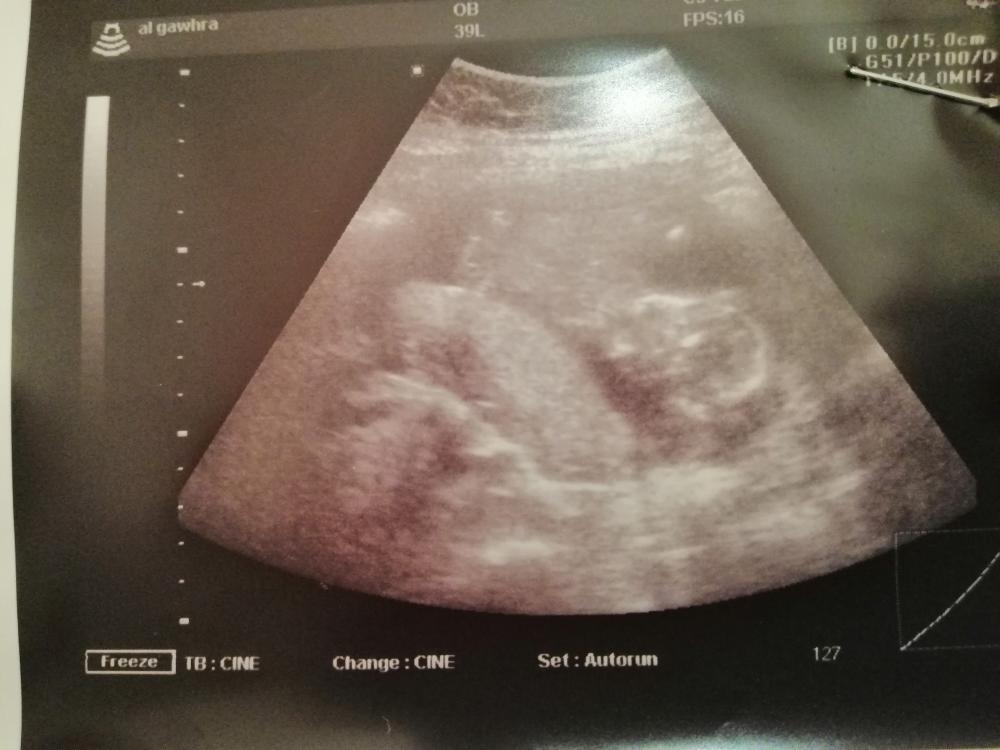

بنات ربي يسعدكم سونار بالاسبوع 16اللي تعرف تقولي

هذا سونار كامل مافي رجول

من مثر ما شفت سونارات تعلمت

عندي اكثر من صوره بس ماعرف من وين حيبان الجنس